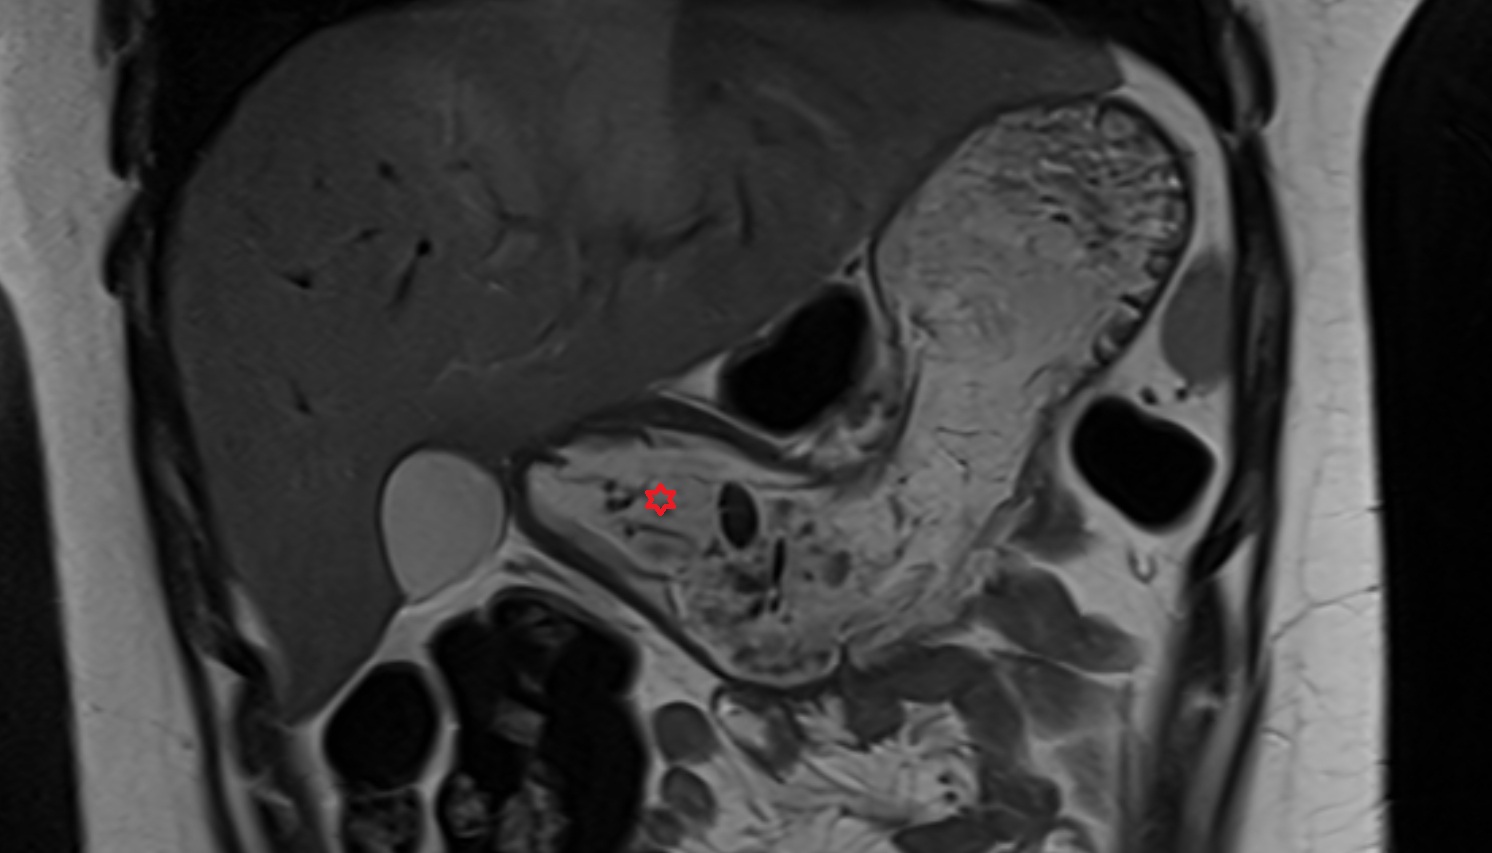

- Uterus

- Ovaries

- Right ovary

- Left ovary

- Fallopian tube